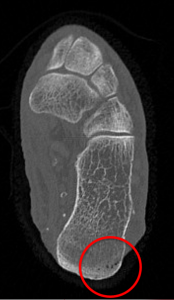

Tomografia Computadorizada

A Tomografia é um super raio X. Assim é possível observar algumas alterações comumente presentes da osteomielite como coleções de pus, ar e sequestro ósseo com maior definição em relação ao RX. No entanto ainda enxergamos apenas a destruição óssea provocada pela osteomielite. Portanto julgamos seus achados observados apenas na osteomielite crônica.